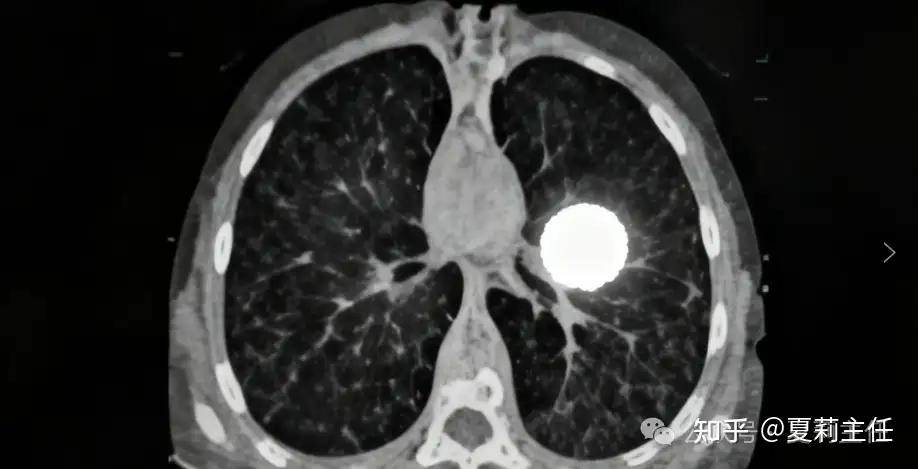

大细胞肺癌02

虽属非小细胞肺癌,但侵袭性极强。癌细胞体积大、生长迅猛,易侵犯周围组织血管,转移速度快(尤其偏爱胸膜、骨骼、脑部)。症状突发且进展快,易因肿瘤压迫出现呼吸困难、胸痛。